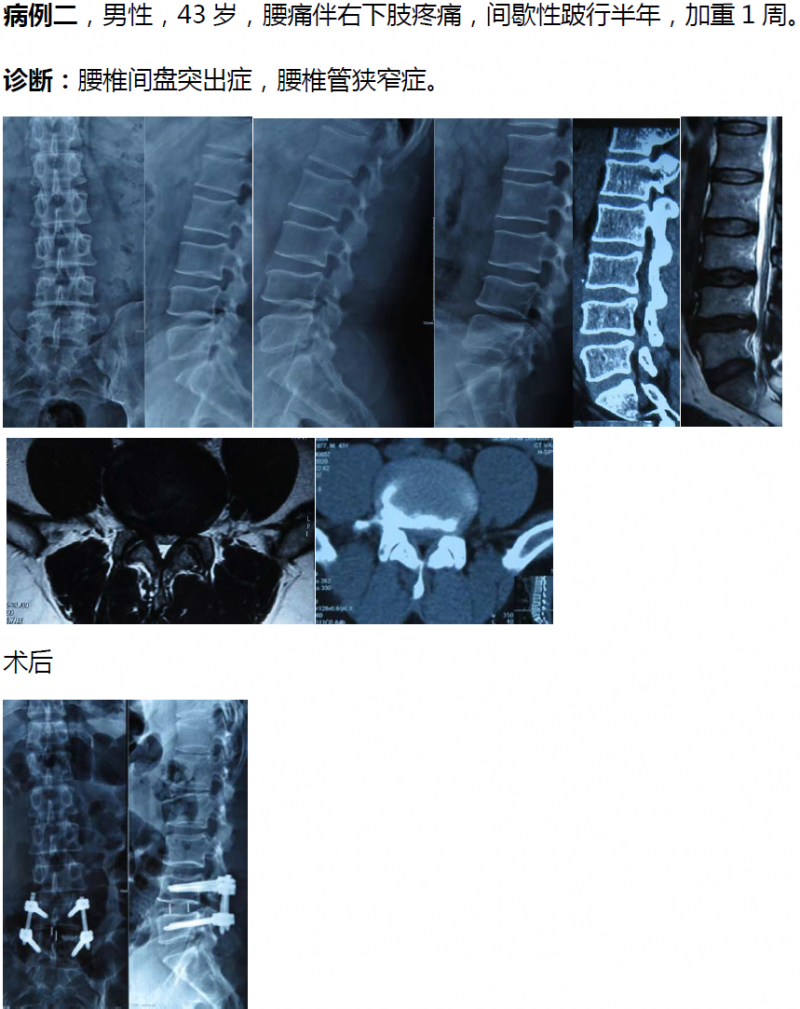

病例分享:(滑动查看)